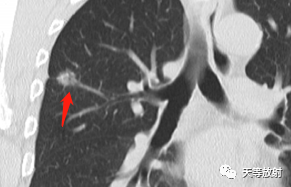

这个层面出现囊腔+实性结节,囊壁较厚。

实性结节呈分叶状改变,邻近胸膜增厚,有牵拉改变,凹陷征。